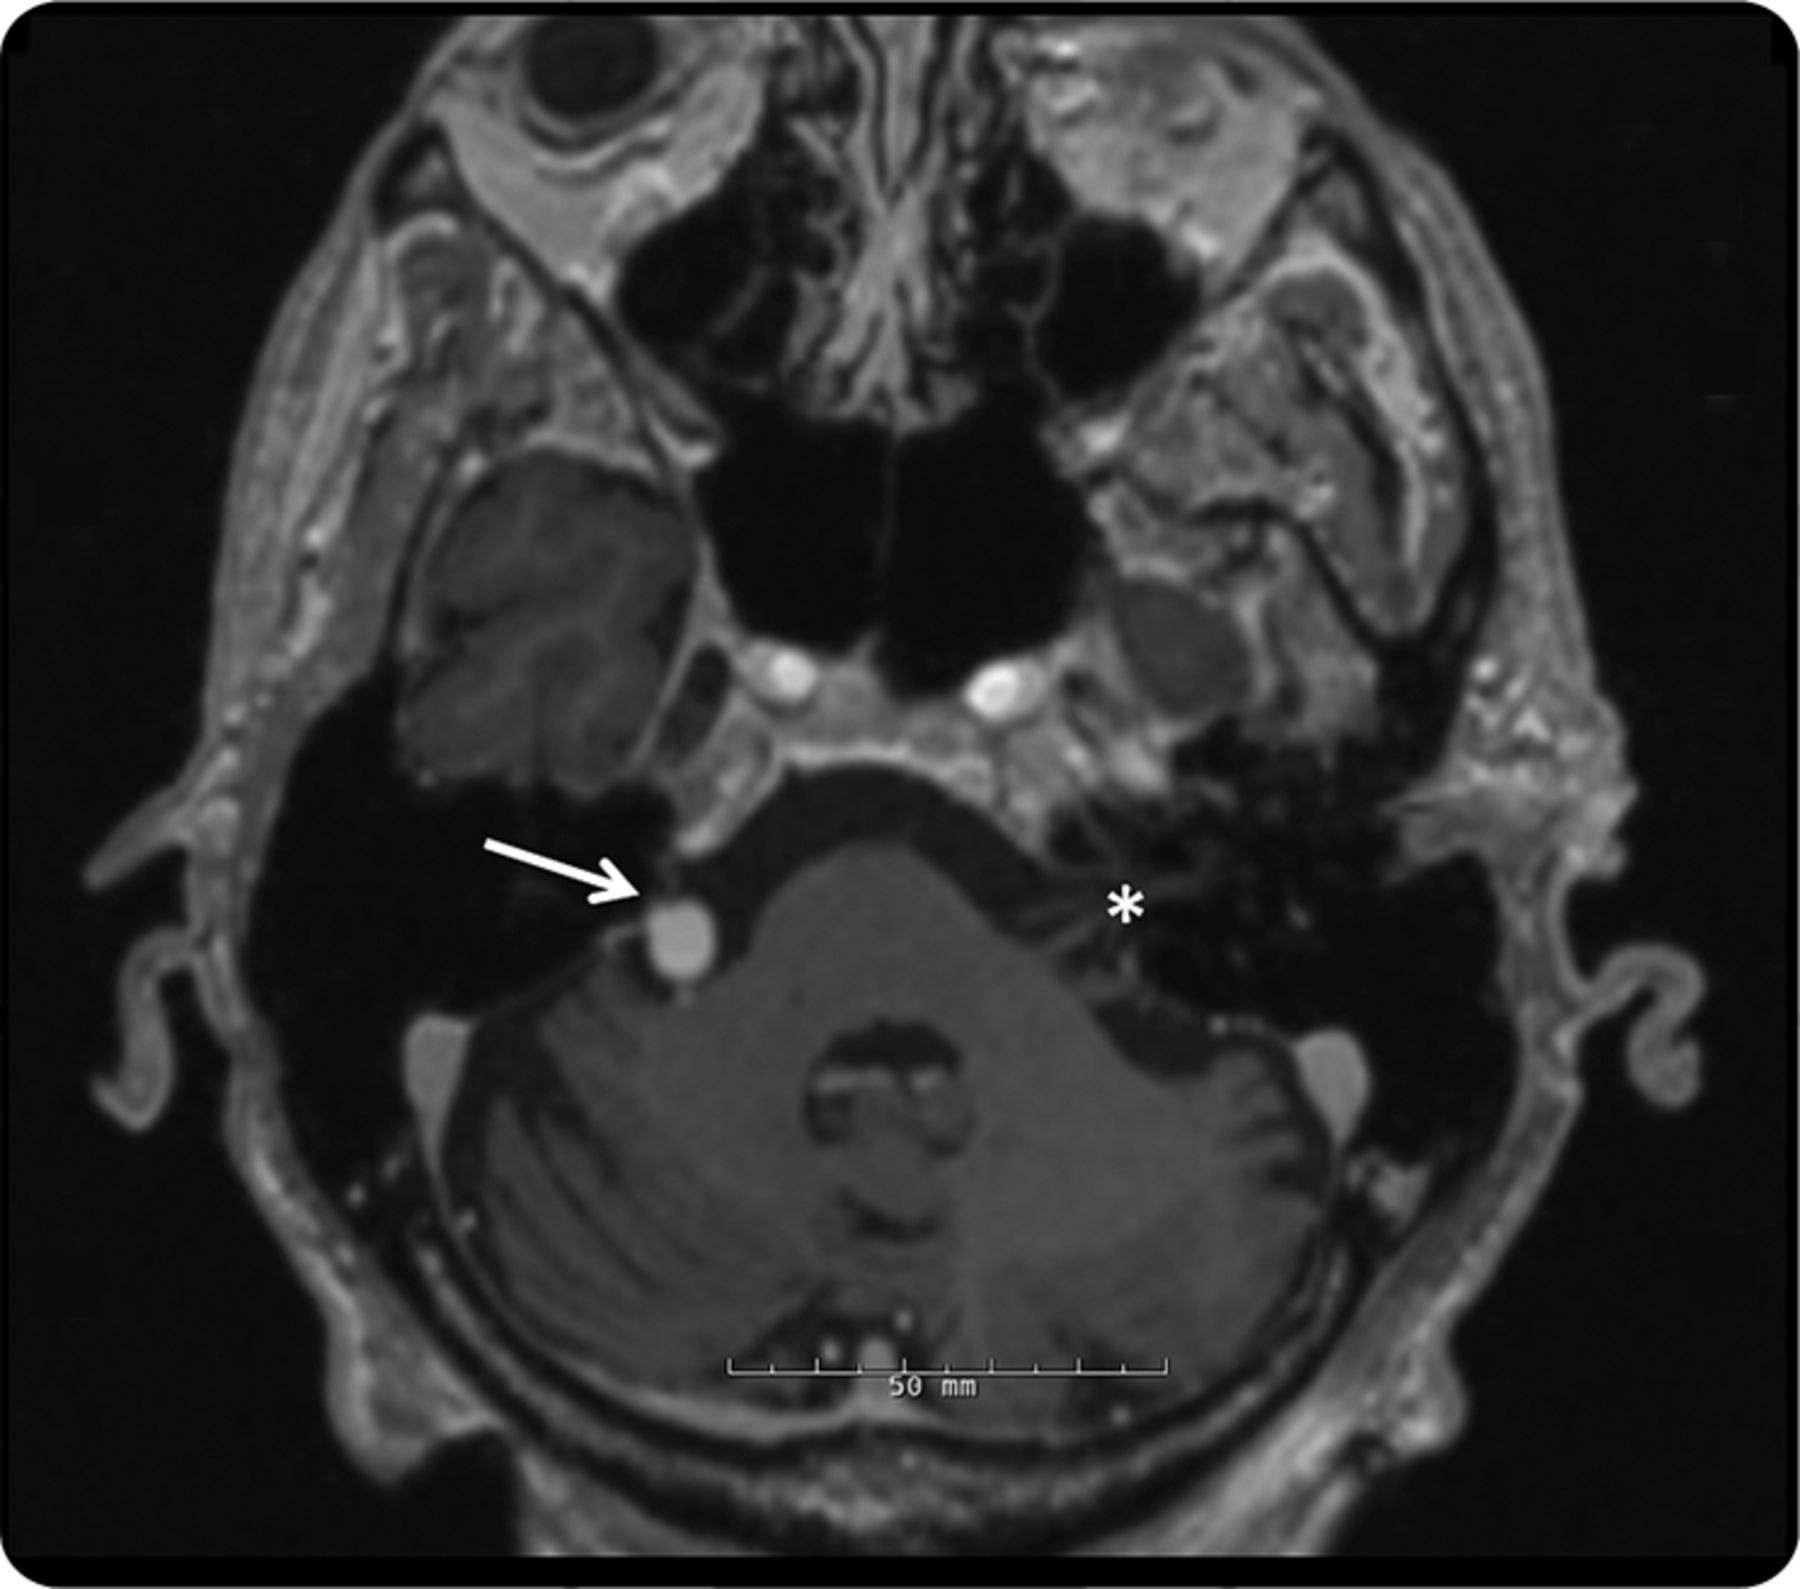

图2

大脑核磁共振,3 d magnetization-prepared快速采集、轴向视图

MRI显示dolichoectatic底动脉扭曲正确的面部神经小脑桥脑角(箭头所指)。作为参考,对侧的面神经显示星号。